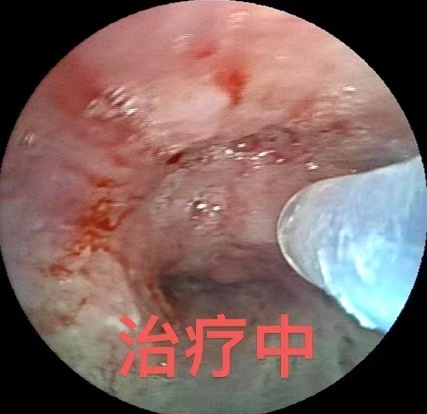

治疗中

面对这一治疗难题,呼吸与危重症医学科二病区主任屈东明博士组织科室介入诊疗团队进行了充分的术前评估和讨论,决定为陈先生实施支气管镜下化学消融治疗。在手术中,诊疗团队使用特制注射穿刺针,对管腔内肿瘤组织多点注射甲苯磺酰胺注射液(PTS)。手术过程顺利,术后肿瘤组织坏死脱落,被阻塞的气道明显畅通,陈先生的临床症状得到了部分改善。